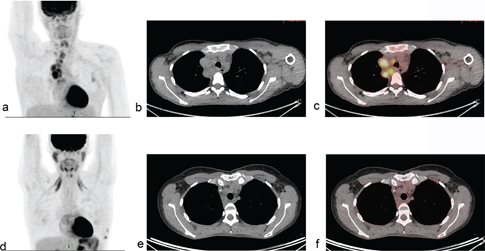

The greatest advantage of PET/CT in lymphoma is that it can accurately separate residual, viable lymphoma from scar tissue, which is often present after therapy (23). The ability to early identify tumor response before tumor shrinkage makes PET/CT as useful tool for early treatment evaluation. Early metabolic response by PET/CT after few cycles of chemotherapy was shown to be highly prognostic for progression-free survival (PFS), with PET-positive patients after two cycles of ABVD having 2-year PFS of 0% versus 96% for those who were PET-negative at the same time point (Figures 2 and 3) (24). This was subsequently confirmed in a larger international series (25). These observations spurred interest in using PET/CT to guide treatment based on early response in both escalation and de-escalation trials (4, 26, 27). These clinical trials have paved the way for more personalized treatment strategies in HL and are described in detail in the sections about management of early- and late-stage HL.

Fig 2

Figure 2. A young woman with a history of progressive swellings, dyspnea, and fever. Biopsy revealed Hodgkin lymphoma. Abnormal FDG-uptake at baseline PET/CT (a,b,c) was confined to enlarged clavicular and mediastinal lymph nodes, i.e., disease stage 2. Interim PET/CT (d,e,f) after two cycles of ABVD (doxorubicin, bleomycin, vinblastine, and dacarbazine) was coherent with complete metabolic response (Deauville Score 2) although lymph nodes remained enlarged on CT scan.

A common language for assessing metabolic response by PET/CT is necessary to ensure that the treatment decisions are reproducible. The international harmonization criteria from 2007 proposed a dichotomous scoring system where mediastinal blood pool activity was recommended as the reference background activity to define PET positivity for a residual mass greater or equal to 2 cm in greatest transverse diameter, whereas background update was to be used for assessment of smaller lesions (28). However, dichotomous scores in lymphoma proved suboptimal. Response-adapted treatment strategies based on interim PET/CT should enable tailoring the risk of false positive/false negative assessments to the question being asked in the trial, which can be done using more granular response reporting (29). The Deauville 5-point score (DS) is now the standard for reporting PET/CT response assessment in lymphoma (Figure 2 and 3) (7). DS was conceived to graduate the intensity of 18F-Fluoro-deoxy-glucose (FDG) uptake in previously identified lymphoma lesions relative to the liver uptake. DS 1 and 2 represent a FDG uptake lower than that of liver, uptake DS 3 represents an intensity of uptake up to that of liver, and DS 4 and 5 represent different degrees of FDG uptake above liver level and new lesions (score 5) (7). For interim and end-of-therapy response assessment in HL, a scores between 1 and 3 are conventionally considered as complete metabolic response (Figure 2) whereas DS 4 or 5 represent active HL (Figure 3) (7). Several studies have shown that the Deauville score is high prognostic in HL using DS 1–3 to define a complete metabolic response (CMR) and DS 4–5 as non-response. In two recently finalized trials of PET-guided de-escalation strategies (HD16 and D18) conducted by the German Hodgkin Study Group, the trials were designed to use DS 1–2 (above the mediastinum) as negative (or equivalent), but further analyses of these trials showed that residual uptake above liver level (DS 4–5) was better in predicting outcomes (3032). In the HD16, 5-year PFS was 93.2% among PET-2-negative patients and 88.4% in PET-2-positive patients (P = .047) when using DS3+ as definition of a positive PET/CT, but when using liver cutoff (DS 4+) for PET-2 positivity, 5-year PFS was 93.1% for PET negative patients vs 80.9% for PET positive patients (P = .0011) (30). In post-hoc analyses of HD18, DS4 was the only risk factor for inferior overall survival in a cohort of patients with DS 1–4 after two cycles of BEACOPP escalated after adjustments for other risk factors (32). The timing of interim PET/CT in HL is conventionally after two courses of chemotherapy, but a negative PET/CT after 1 cycle also has a very high negative predictive value (2-year PFS 98%) and is currently used in clinical trials of very early PET/CT adapted treatment strategies (NCT03517137) (33).